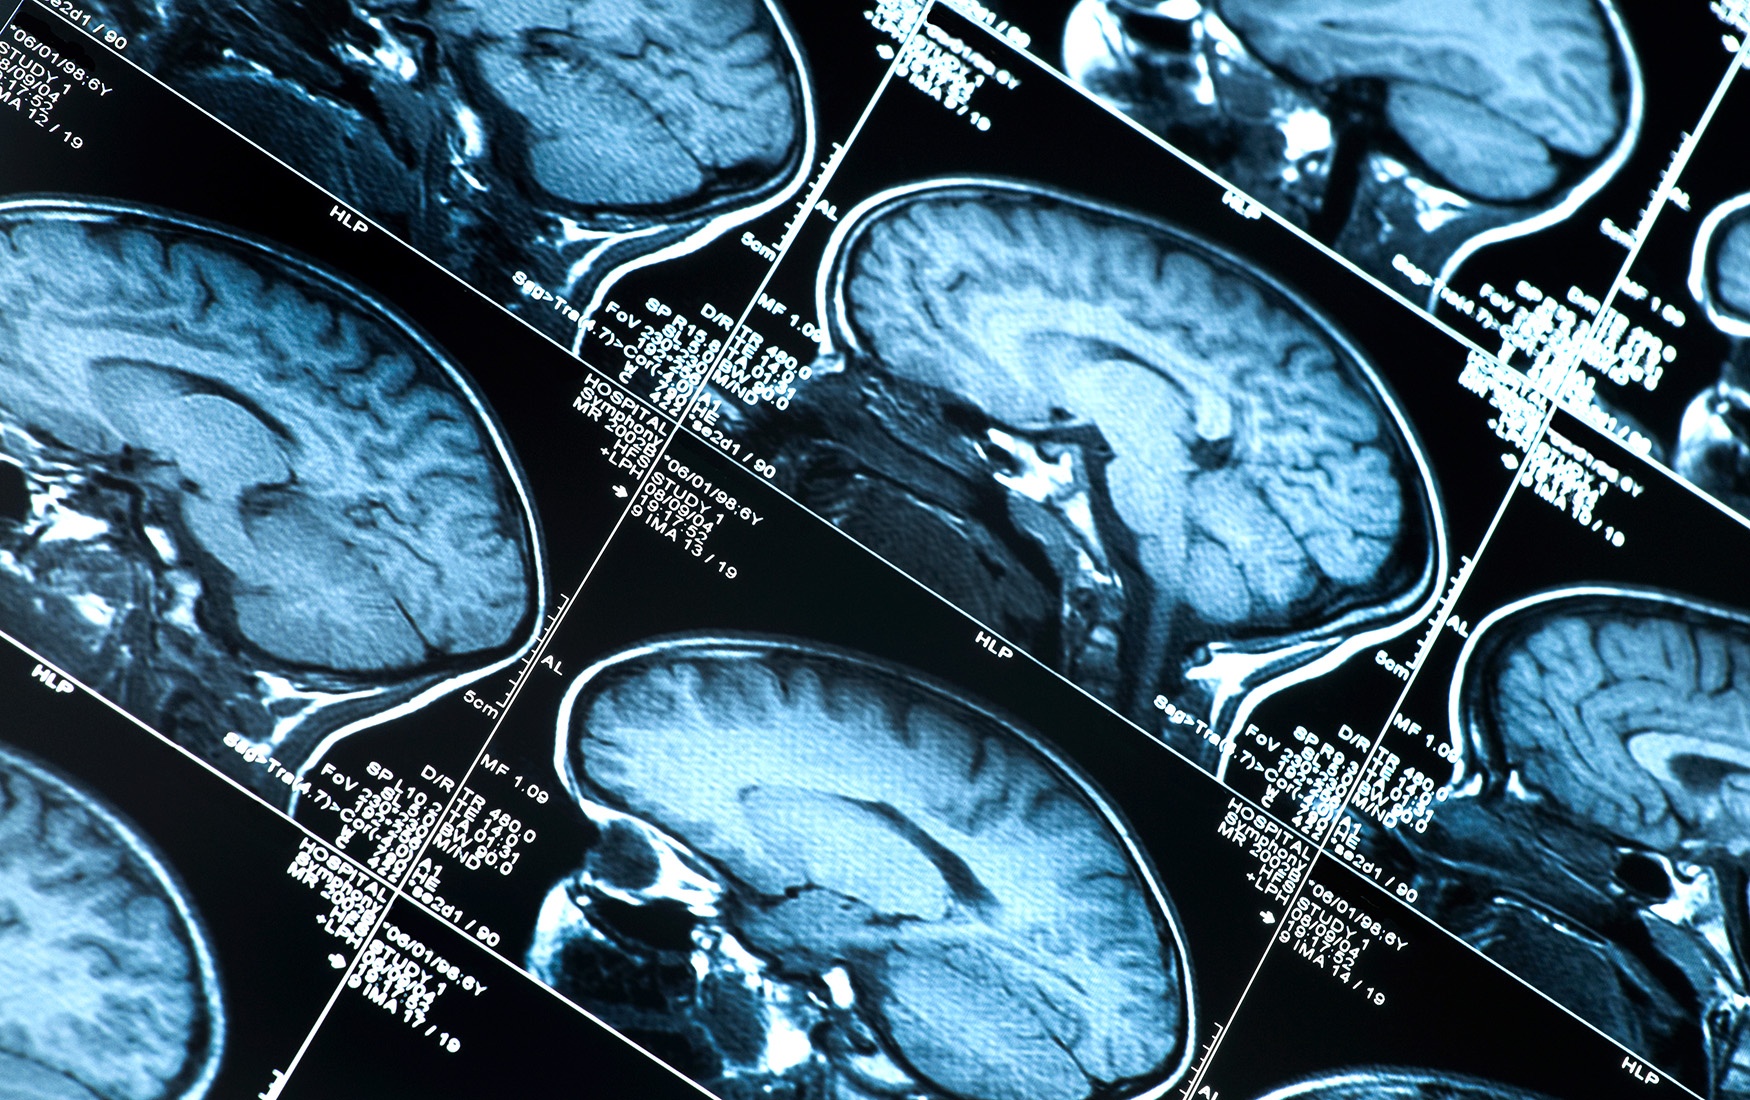

Метаболизм лобной коры и внутренняя уязвимость

Итак, мы подняли важный вопрос, касающийся и социальной, и когнитивной функции лобной коры. Все наши сослагательные «если» — если бы я был там-то и там-то, то сделал бы то-то и то-то или если бы я это увидел, то сказал бы так-то и так-то — дирижируются лобной корой. Она занимается правилами. Во всяких непредвиденных обстоятельствах включаются другие части мозга, но в случаях, когда дело касается выполнения правил, рулит именно лобная кора. Подумайте, например, о правиле горшка, которое мы выучиваем в три года: не писать сразу, как только появляется желание. Лобная кора находит средства для исполнения этого правила, увеличив свое влияние на нейроны, управляющие мускулатурой мочевого пузыря.

Более того, мантра «самодисциплина — это правильно», изготовленная в лобной коре с помощью отказа от соблазнительного печенья, срабатывает и тогда, когда приходится экономить для увеличения будущих пенсионных накоплений. Нейроны лобной коры — настоящие универсалы: их отростки расходятся широко, выполняя самую разнообразную работу.

На эту работу требуется много энергии, поэтому не случайно, что в лобной коре уровень метаболизма исключительно высокий, равно как и активность генов, отвечающих за выработку энергии. «Сила воли» — не просто метафора, она указывает на конечный (энергетический) ресурс, требующийся на поддержание самоконтроля. Мало того, что эти лобные нейроны дорого нам достаются, так они еще и весьма уязвимы — как и все «дорогие» клетки. Потому именно в лобной коре неврологические инсульты случаются гораздо чаще.